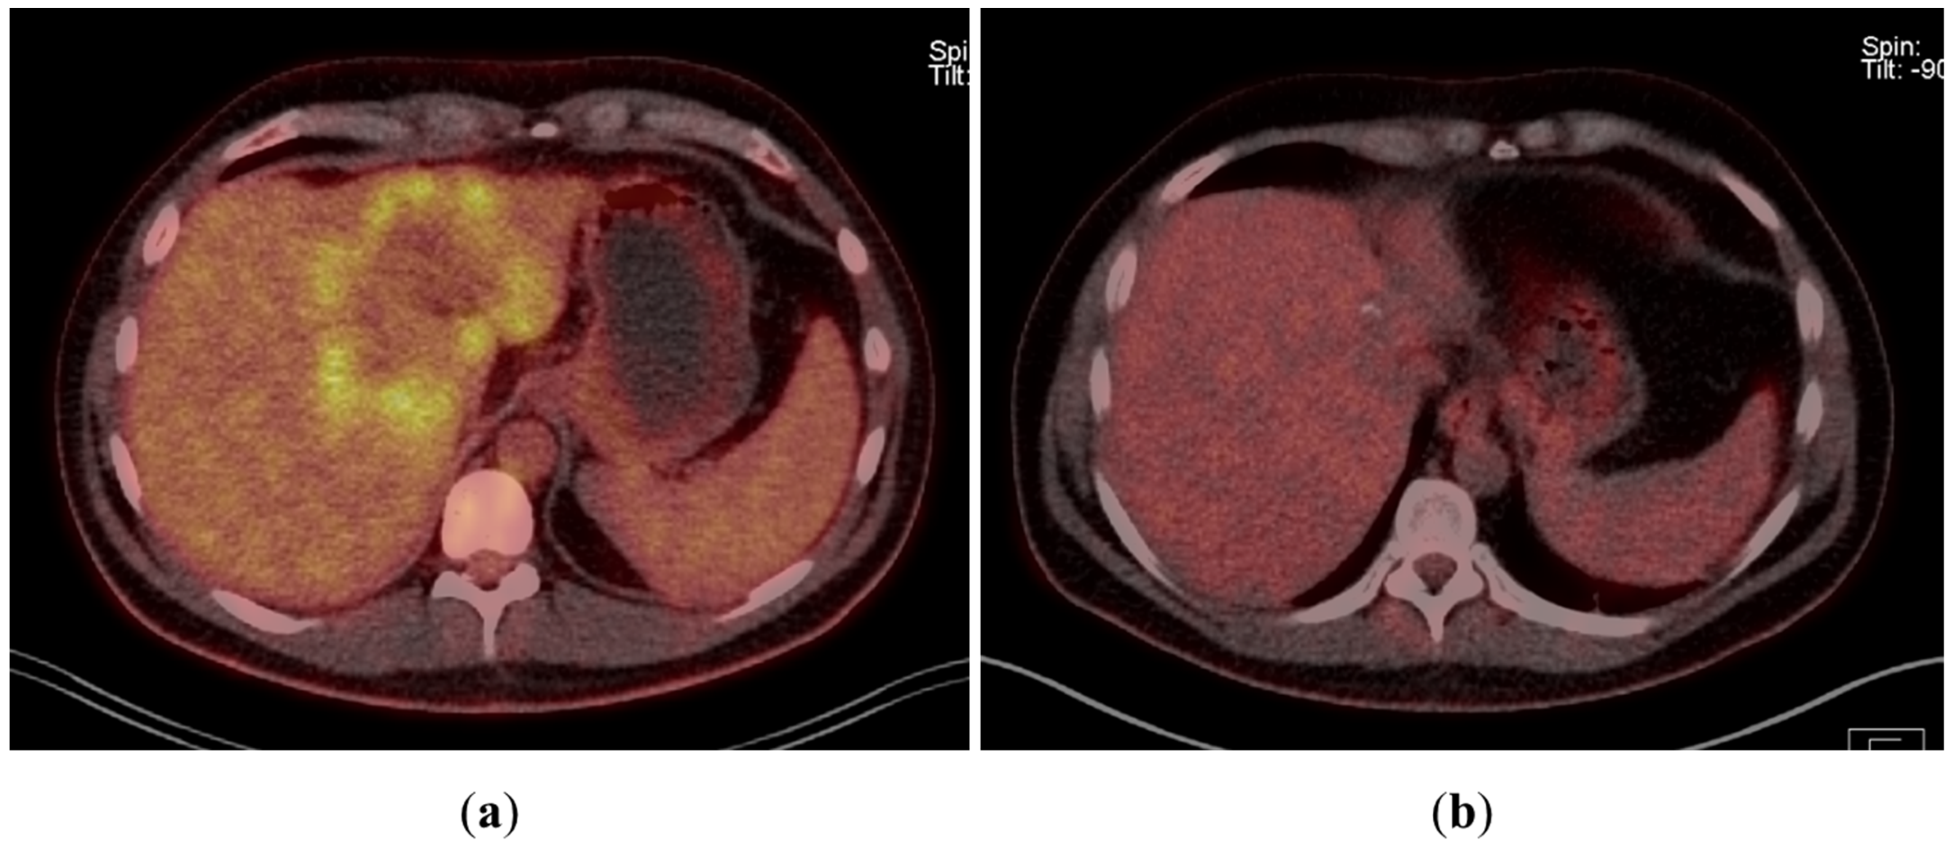

A 43-year-old man went because of persistent fatigue to the general practitioner. The diagnostic showed a large tumor within the central liver (see Figure 1a), which was biopsy-proven as a moderate-differentiated intrahepatic cholangiocarcinoma. An extrahepatic tumor spread could be ruled out (applying an FDG-PET-CT scan, see Figure 2a). Due to the invasion of the hepatic veins, which precluded a primary resection, chemotherapy with cisplatin / gemcitabine was initiated. The tumor showed a partial response (see Figure 1b). We decided to perform surgical exploration with the intent of an ex situ liver resection. Due to an invasion in liver segment VII, even an extended left trisegmentectomy was not possible. We performed an SIRT of both liver lobes resulting in a further, even metabolic (Standardized Uptake Value, SUVmean of the tumor in the initial PET scan: 7.3; SUVmean after treatment: 3.0), response of the tumor (see Figure 2a,b). The CA19-9 levels were always below the reference value. Twenty-two months after the initial diagnosis, the patient could be transplanted with a right living donor lobe from a friend. Histopathologic examination showed an intrahepatic cholangiocarcinoma with a maximum diameter of 6.3 cm. The tumor stage was ypT3, N0, L0, V0, Pn0, R0. Currently, 17 months after the LDLT, the patient is recurrence-free and in good clinical health (see Figure 3). The most recent CA19-9 level is 21.3 U/mL (reference value < 27.0 U/mL).

Figure 1. (a): Tumor load at the initial presentation of the patient. (b) Tumor load after cisplatin/gemcitabine therapy. Note the shrinkage of the left liver lobe.